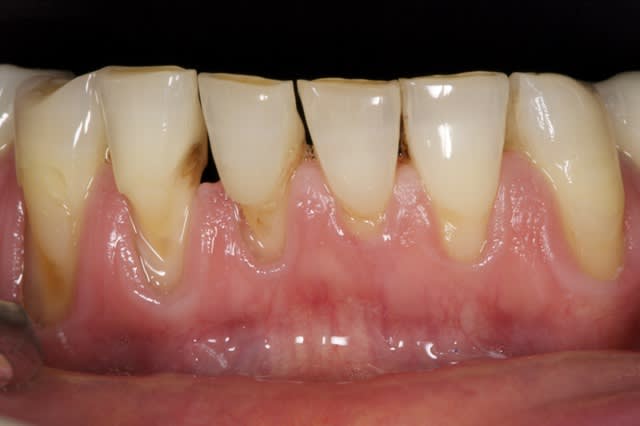

Cas d'urgence aujourd'hui. Vous avez 10 mn. Je suis au contact du public et que ca soit bien remboursé hein ! Reste 32 33 34 mobilité +++++++++.

Notons apparemment la bonne prise en charge des cerams par la mutuelle, mais pas la paro. Dommage ! -))))))

Ce pays est foutu. -)))))